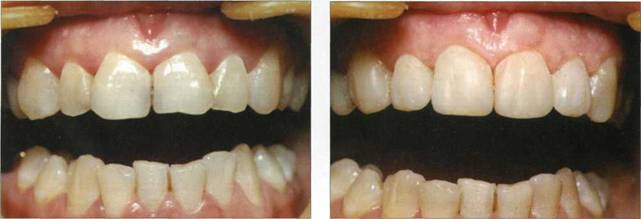

Клинический пример 23

Пациентке 19 лет. Флюороз. Произведена реконструкция первых премоляров, клыков, резцов верхней челюсти материалом "Charisma" фирмы "Heraeus KULZER".

Рис. 791. Этап препарирования зубов

Рис. 792. Конечный результат